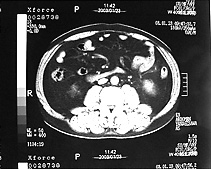

さらに、上半身肥満はお腹の皮の下に脂肪の多い「皮下脂肪型肥満」と内臓のまわりに脂肪が多い「内臓脂肪型肥満」に分けられます。そして、内臓脂肪型肥 満が2型糖尿病、高脂血症、高血圧症などと深く関係しています。内臓脂肪が多いかどうかは、腹部CTスキャンでみるとよくわかります(図2)。

図2 腹部のCT写真 | |